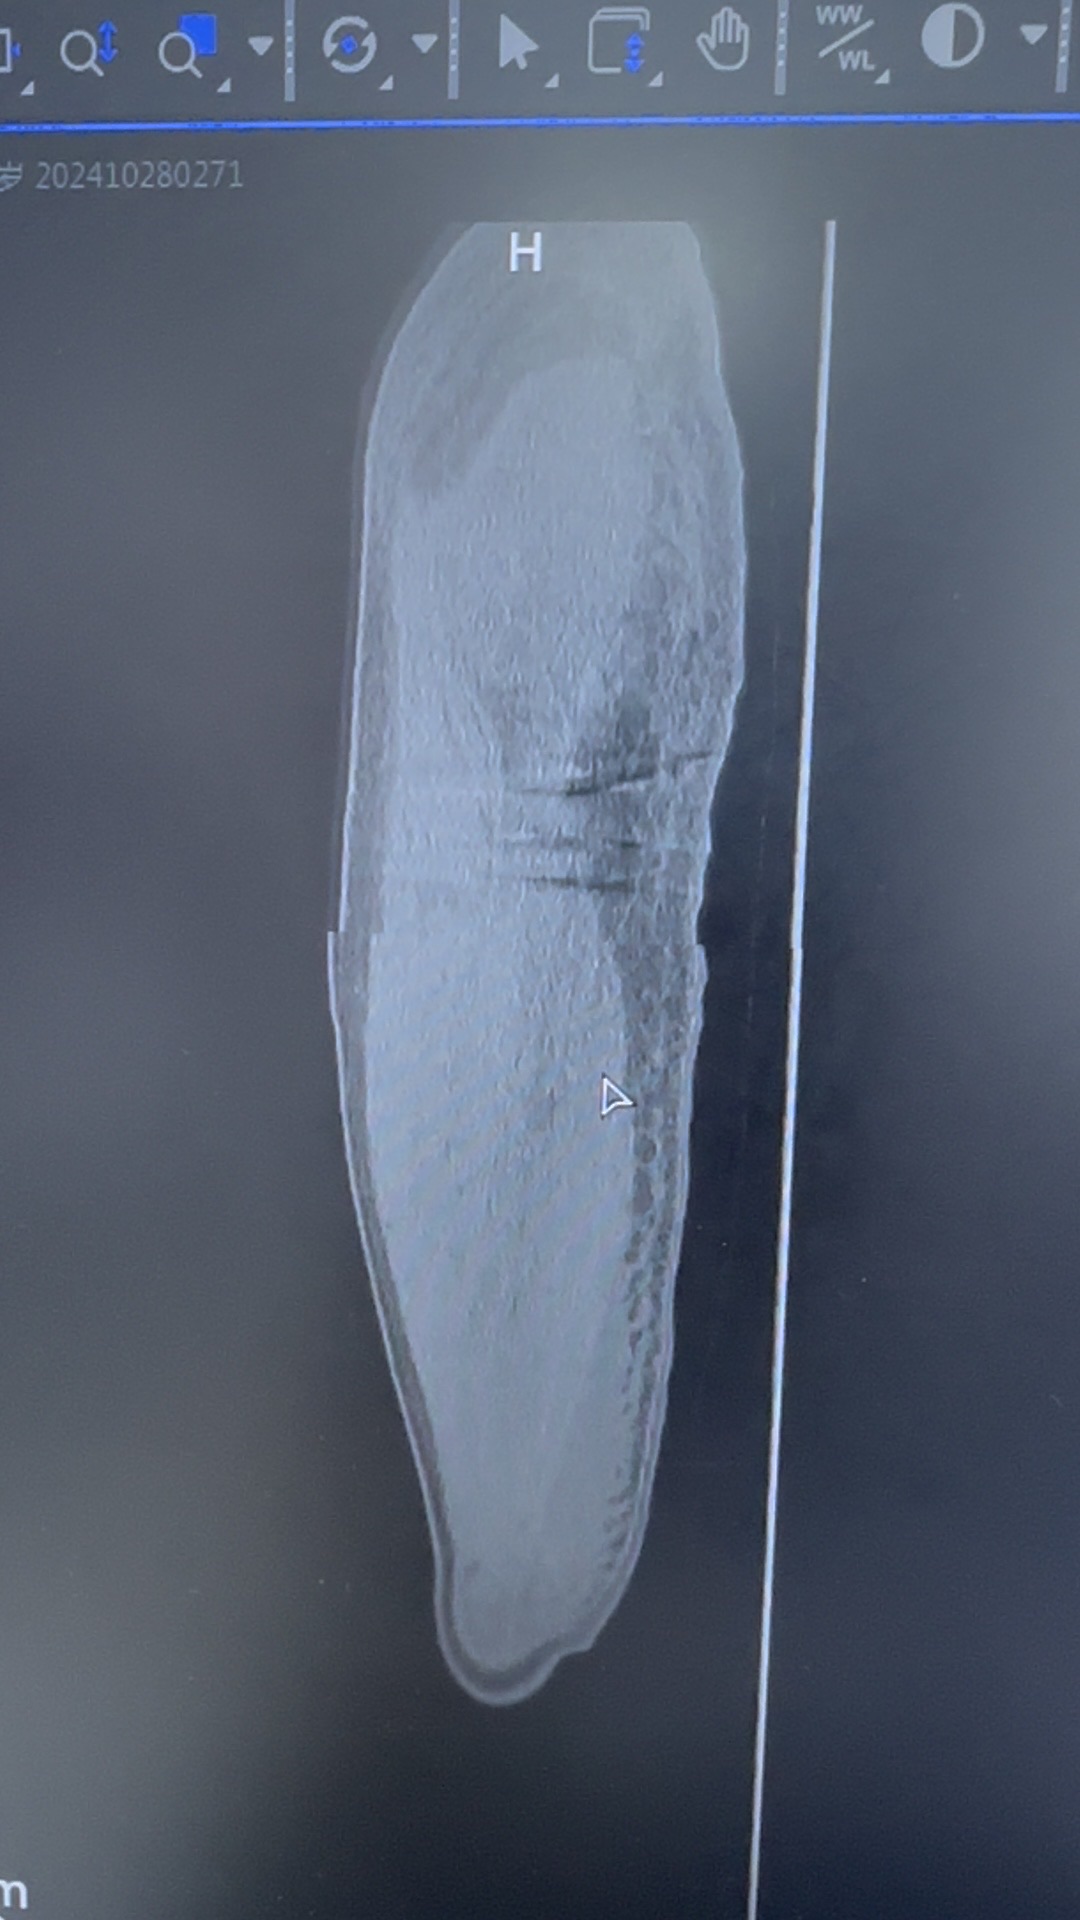

【患者信息】:51岁,男性,高处坠落伤

【主诉】:摔倒致右髋部肿痛活动受限2天入院

【临床诊断】:粗隆下骨折,seinsheimer Ⅴ型

【治疗经过及结果】:切开复位内固定

螺旋刀片位置不佳的原因在哪?复位欠佳?髋内翻?内固定开口偏后?主钉深度不够?